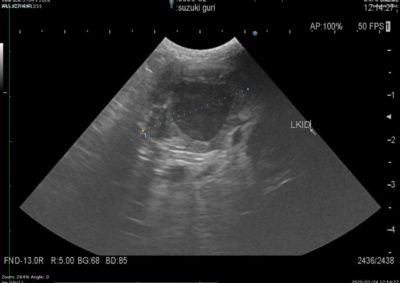

軟部組織外科 注意 ボタンをクリックした先に、治療中および手術中の画像が説明で使用されている場合がございます。 そのような画像に弱い方は閲覧なさらないようお願いいたします。 軟部組織外科 異物による唾液腺の穿孔 軟部組織外科 犬の尿管結石に対する結石摘除 救急・集中治療軟部組織外科 猫の尿管結石に対する尿管切除吻合術#11 軟部組織外科 PSS 犬の門脈体循環シャント 軟部組織外科 猫のPSS 軟部組織外科救急・集中治療 胆嚢摘出 軟部組織外科 予防的胃固定術 Lap−Gastropexy 軟部組織外科 特発性出血性心タンポナーゼ 軟部組織外科 猫の腎膿瘍 軟部組織外科 犬の特発性乳び胸 軟部組織外科 短頭種気道症候群 軟部組織外科 犬の腟脱 <«789101112131415> 症例カテゴリー 放射線治療整形外科軟部組織外科脳神経外科内科腫瘍外科救急・集中治療リハビリテーション科腫瘍内科内視鏡科脳神経科呼吸器外科中医・漢方猫の腎移植循環器科